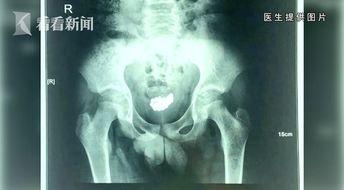

3. 疾病防治:这类视频针对尿道相关疾病,如尿路感染、尿道结石等,介绍病因、症状、治疗方法等。